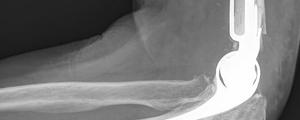

Een prothese vervangt het ellebooggewricht door een metalen component. Het heeft als voornaamste doel een niet-functionerend gewricht te vervangen. Enerzijds voor vergevorderde en pijnlijke slijtage (artrose), anderzijds voor zeer complexe (niet-reconstrueerbare) breuken in en rond de elleboog.

Een elleboogprothese biedt een zeer goede oplossing voor pijn, mobiliteit – en functieverlies, maar is zeer gevoelig aan slijtage en loslating. Om beide redenen is een elleboogprothese onderworpen aan zeer strenge krachtsrestricties. Deze beperkingen horen strikt nageleefd te worden, als garantie op een zo lang mogelijke overleving van de prothese.